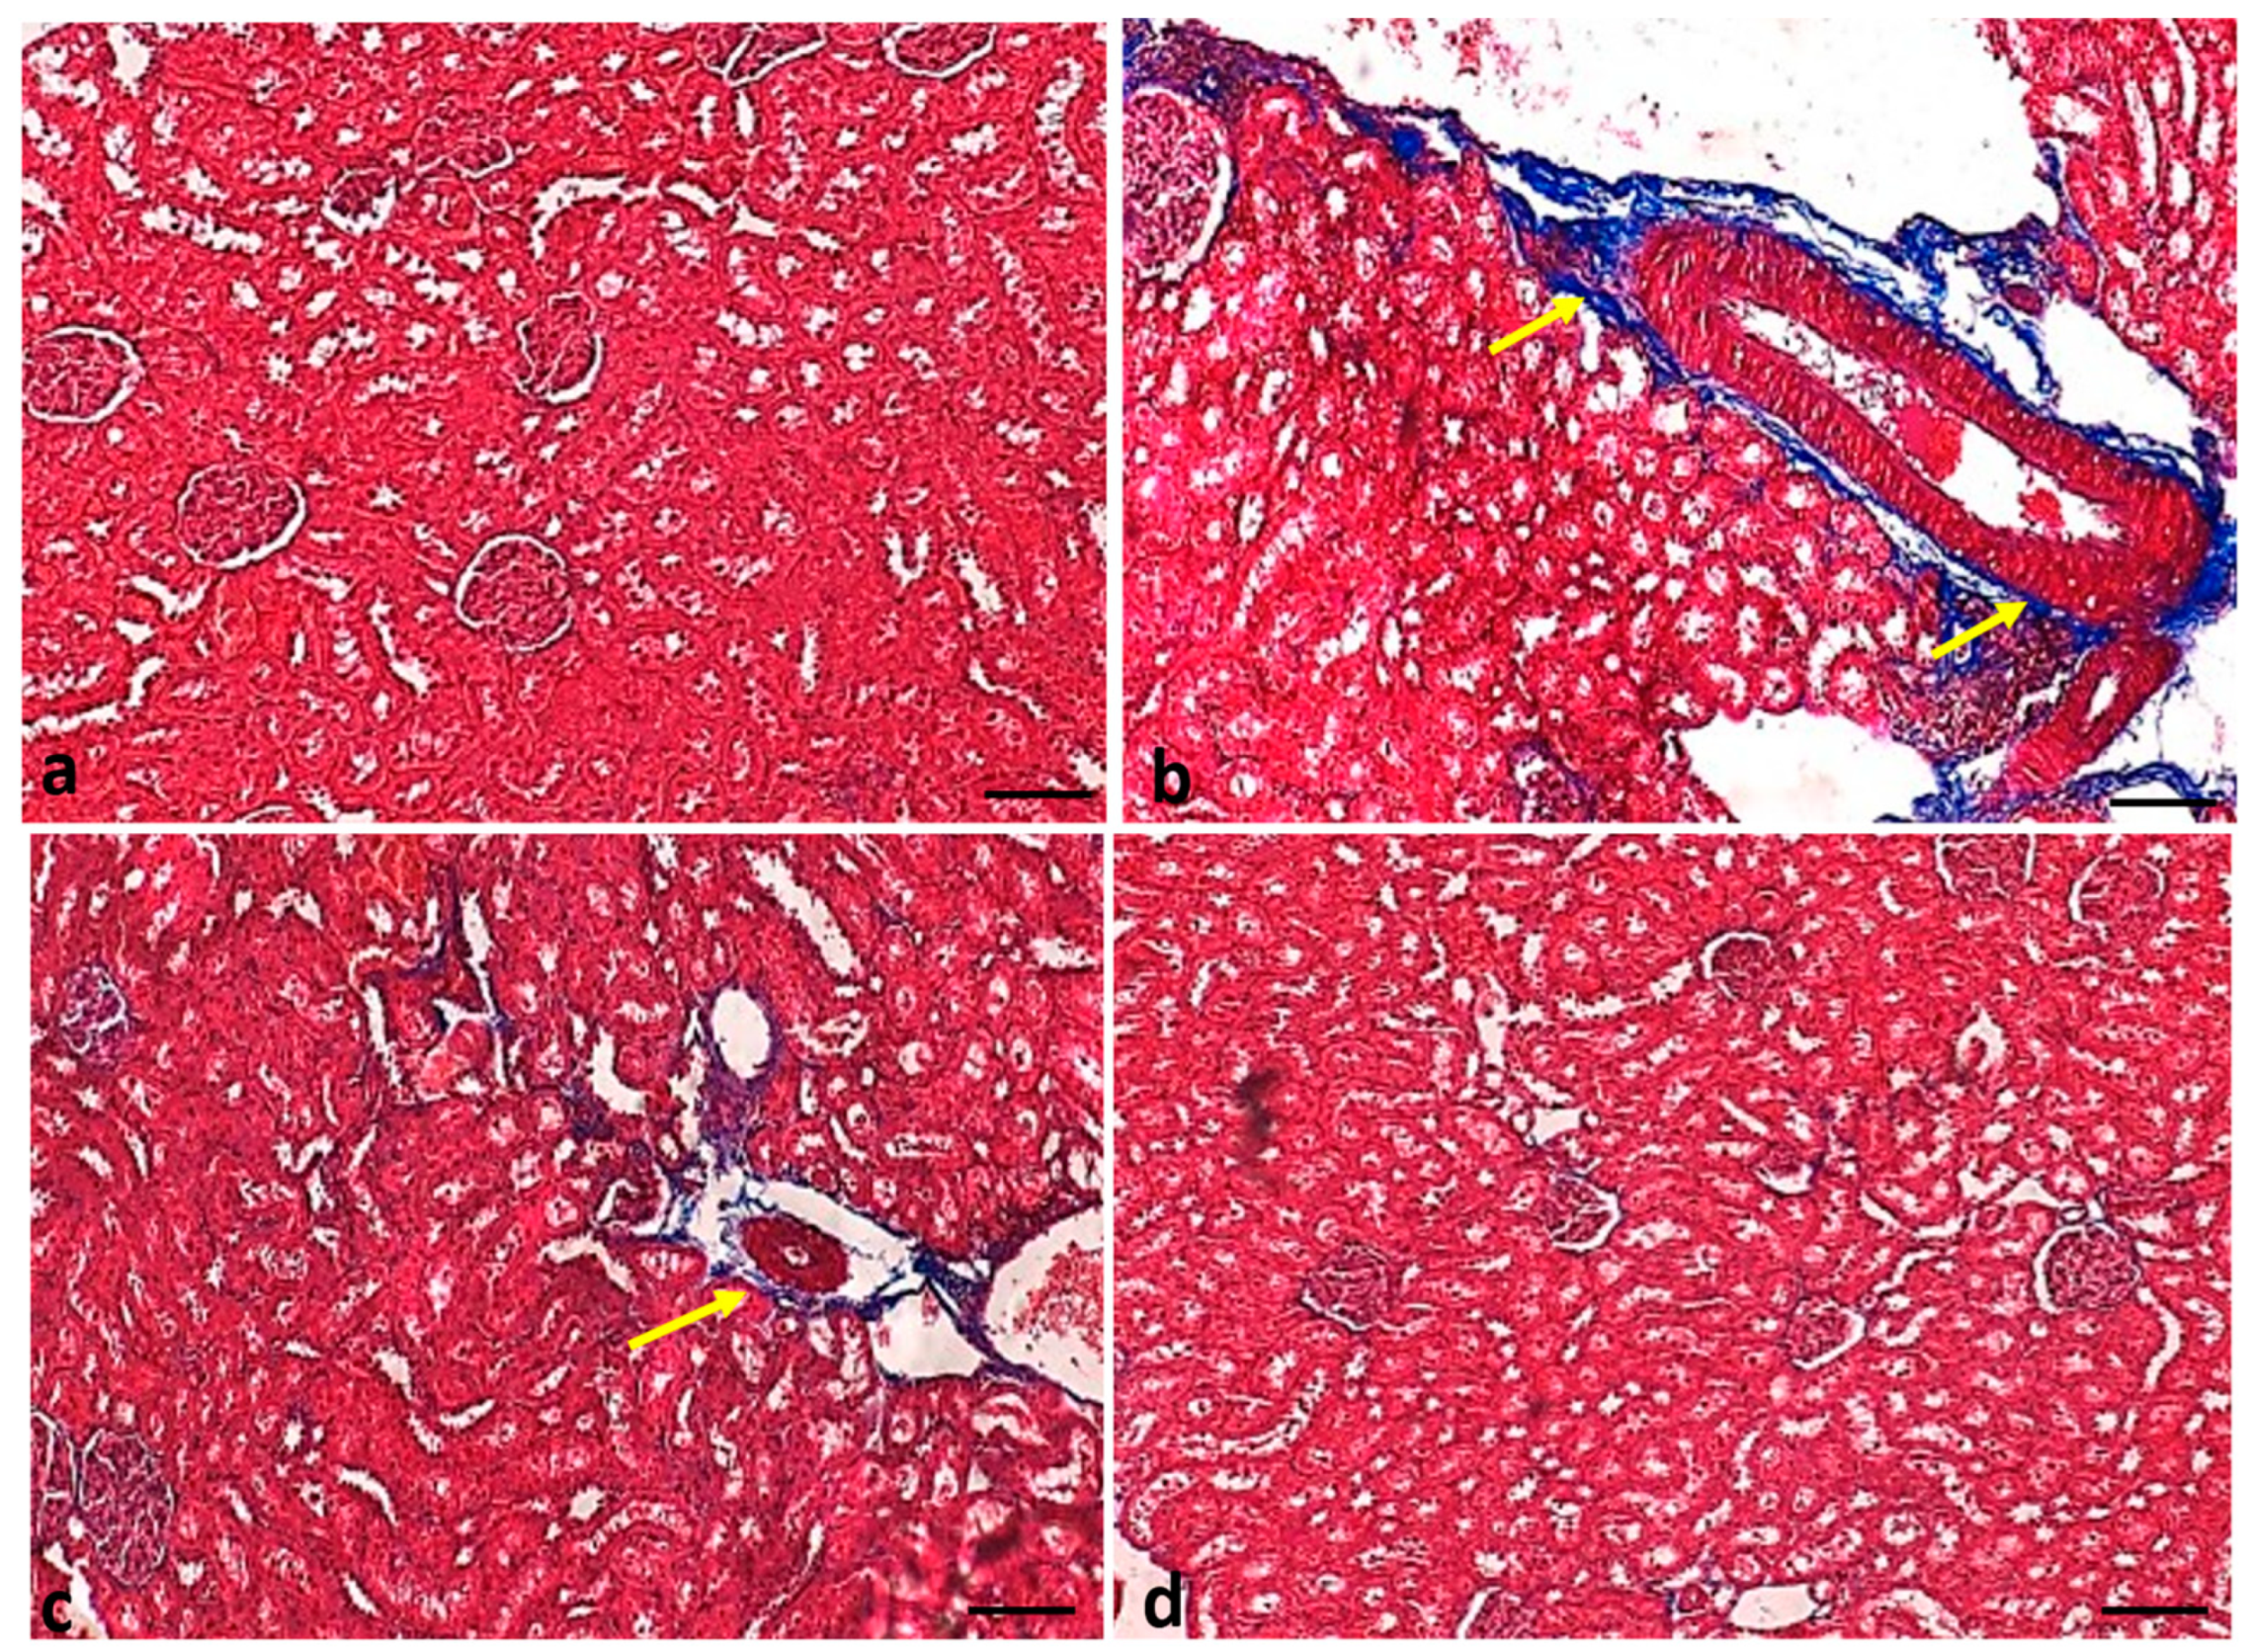

2.8. Effect of Curcumin Treatments on Renal Fibrosis

4.11. Fibrosis Evaluation Using Masson Trichrome and Sirius Red Staining